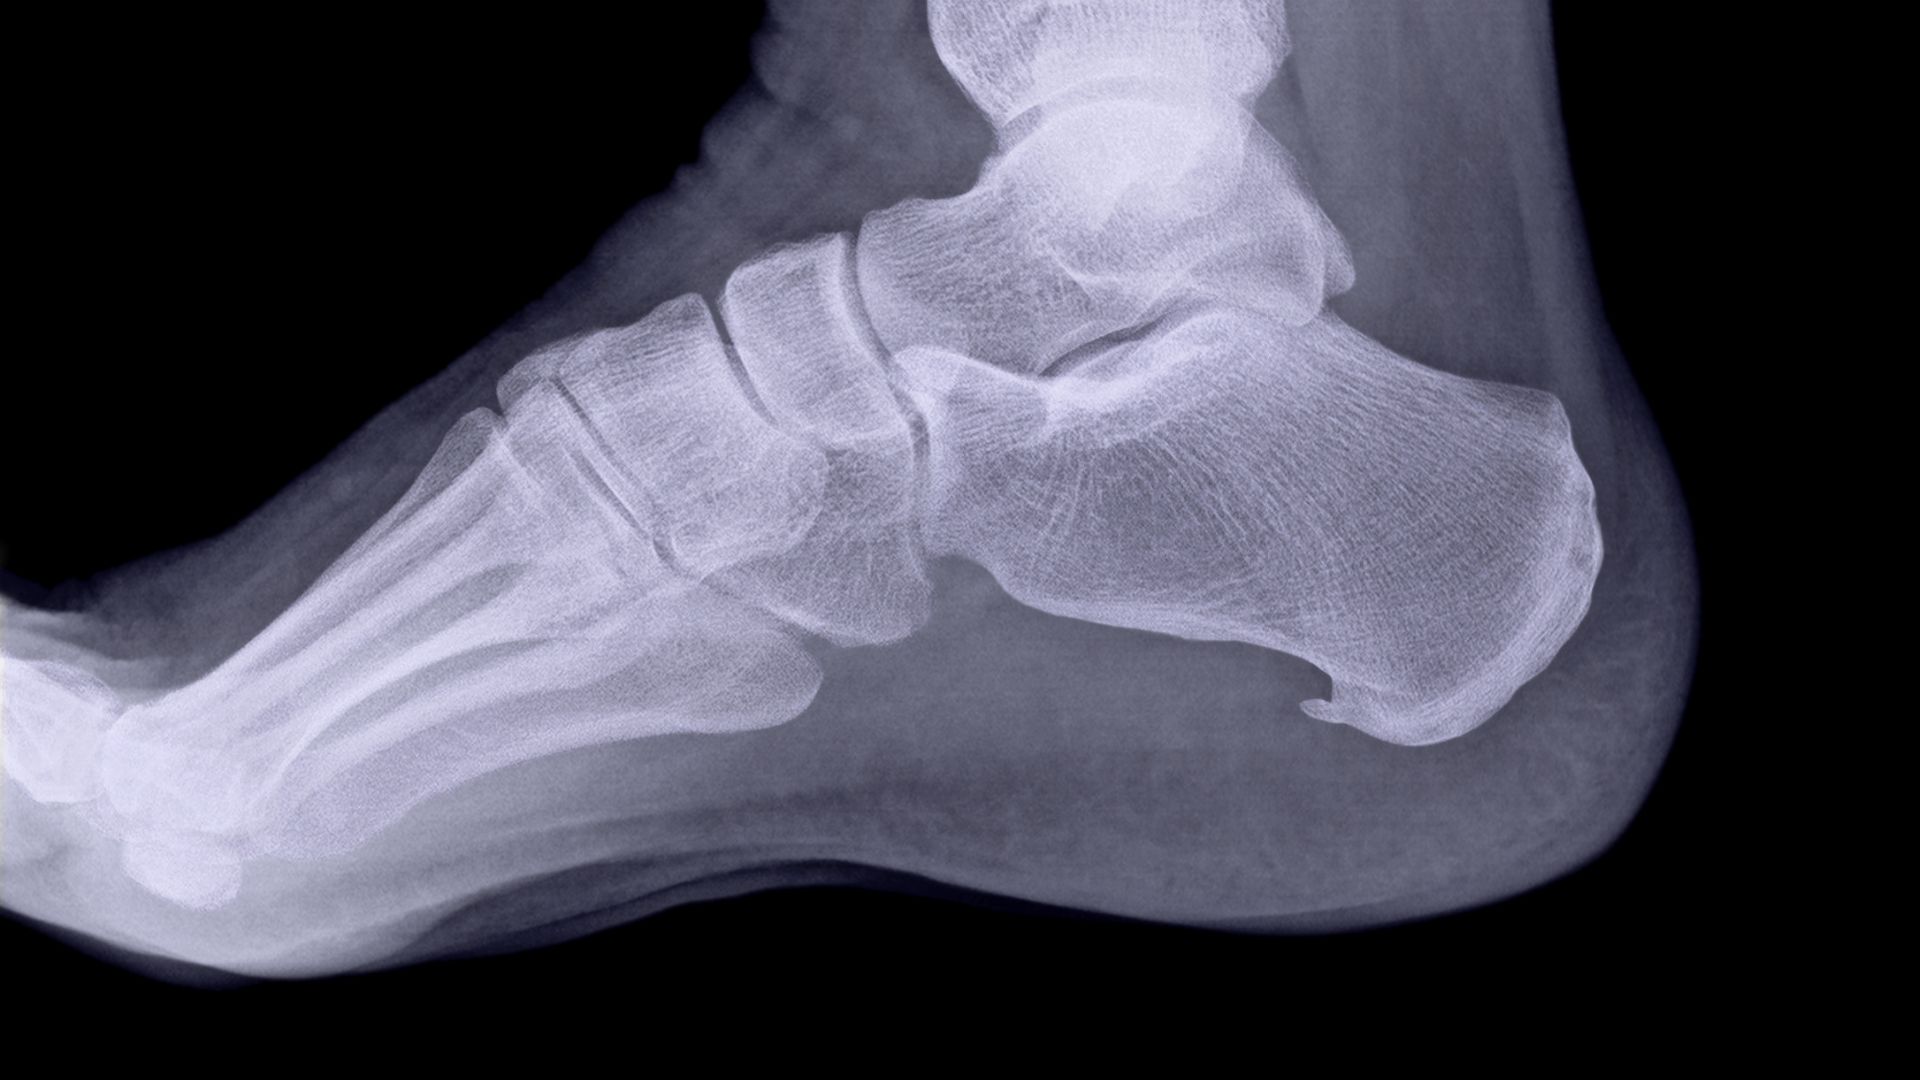

Die Diagnose ist relativ einfach zu Stellen. In den meisten Fällen reicht es schon wenn ein Patient seine Beschwerden beschreibt. Daneben ist die Stelle Druckempfindlich, sicher im Vergleich zum anderen Bein. Um 100% sicher zu sein kannst du mittels eines Röntgenbildes beim Arzt eine vollständige Diagnose bekommen. Auf dem Bild sieht man dann einen Sporn.

Wenn die Sehne ständig Belastet wird kann dies zu Micro Rissen in dem Übergang zwischen Sehnenplatte und Knochen führen. Dein Körper reagiert auf diese kleinen Micro Risse mit Kalkablagerungen. Im Verlauf der Zeit wird dieser Sporn immer grösser und grösser und die Beschwerden steigen.